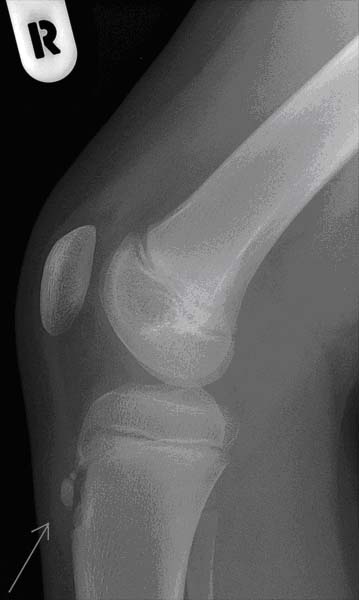

При оценке лабораторных исследований никаких отклонений от нормы не находят. Среди инструментальных исследований особое значение имеет рентгенография пораженного сустава, которая позволяет визуализировать патологию бугристости большеберцовой кости.

- Отделение отдельных костных фрагментов от большеберцовой кости, установленное с помощью рентгенографии.